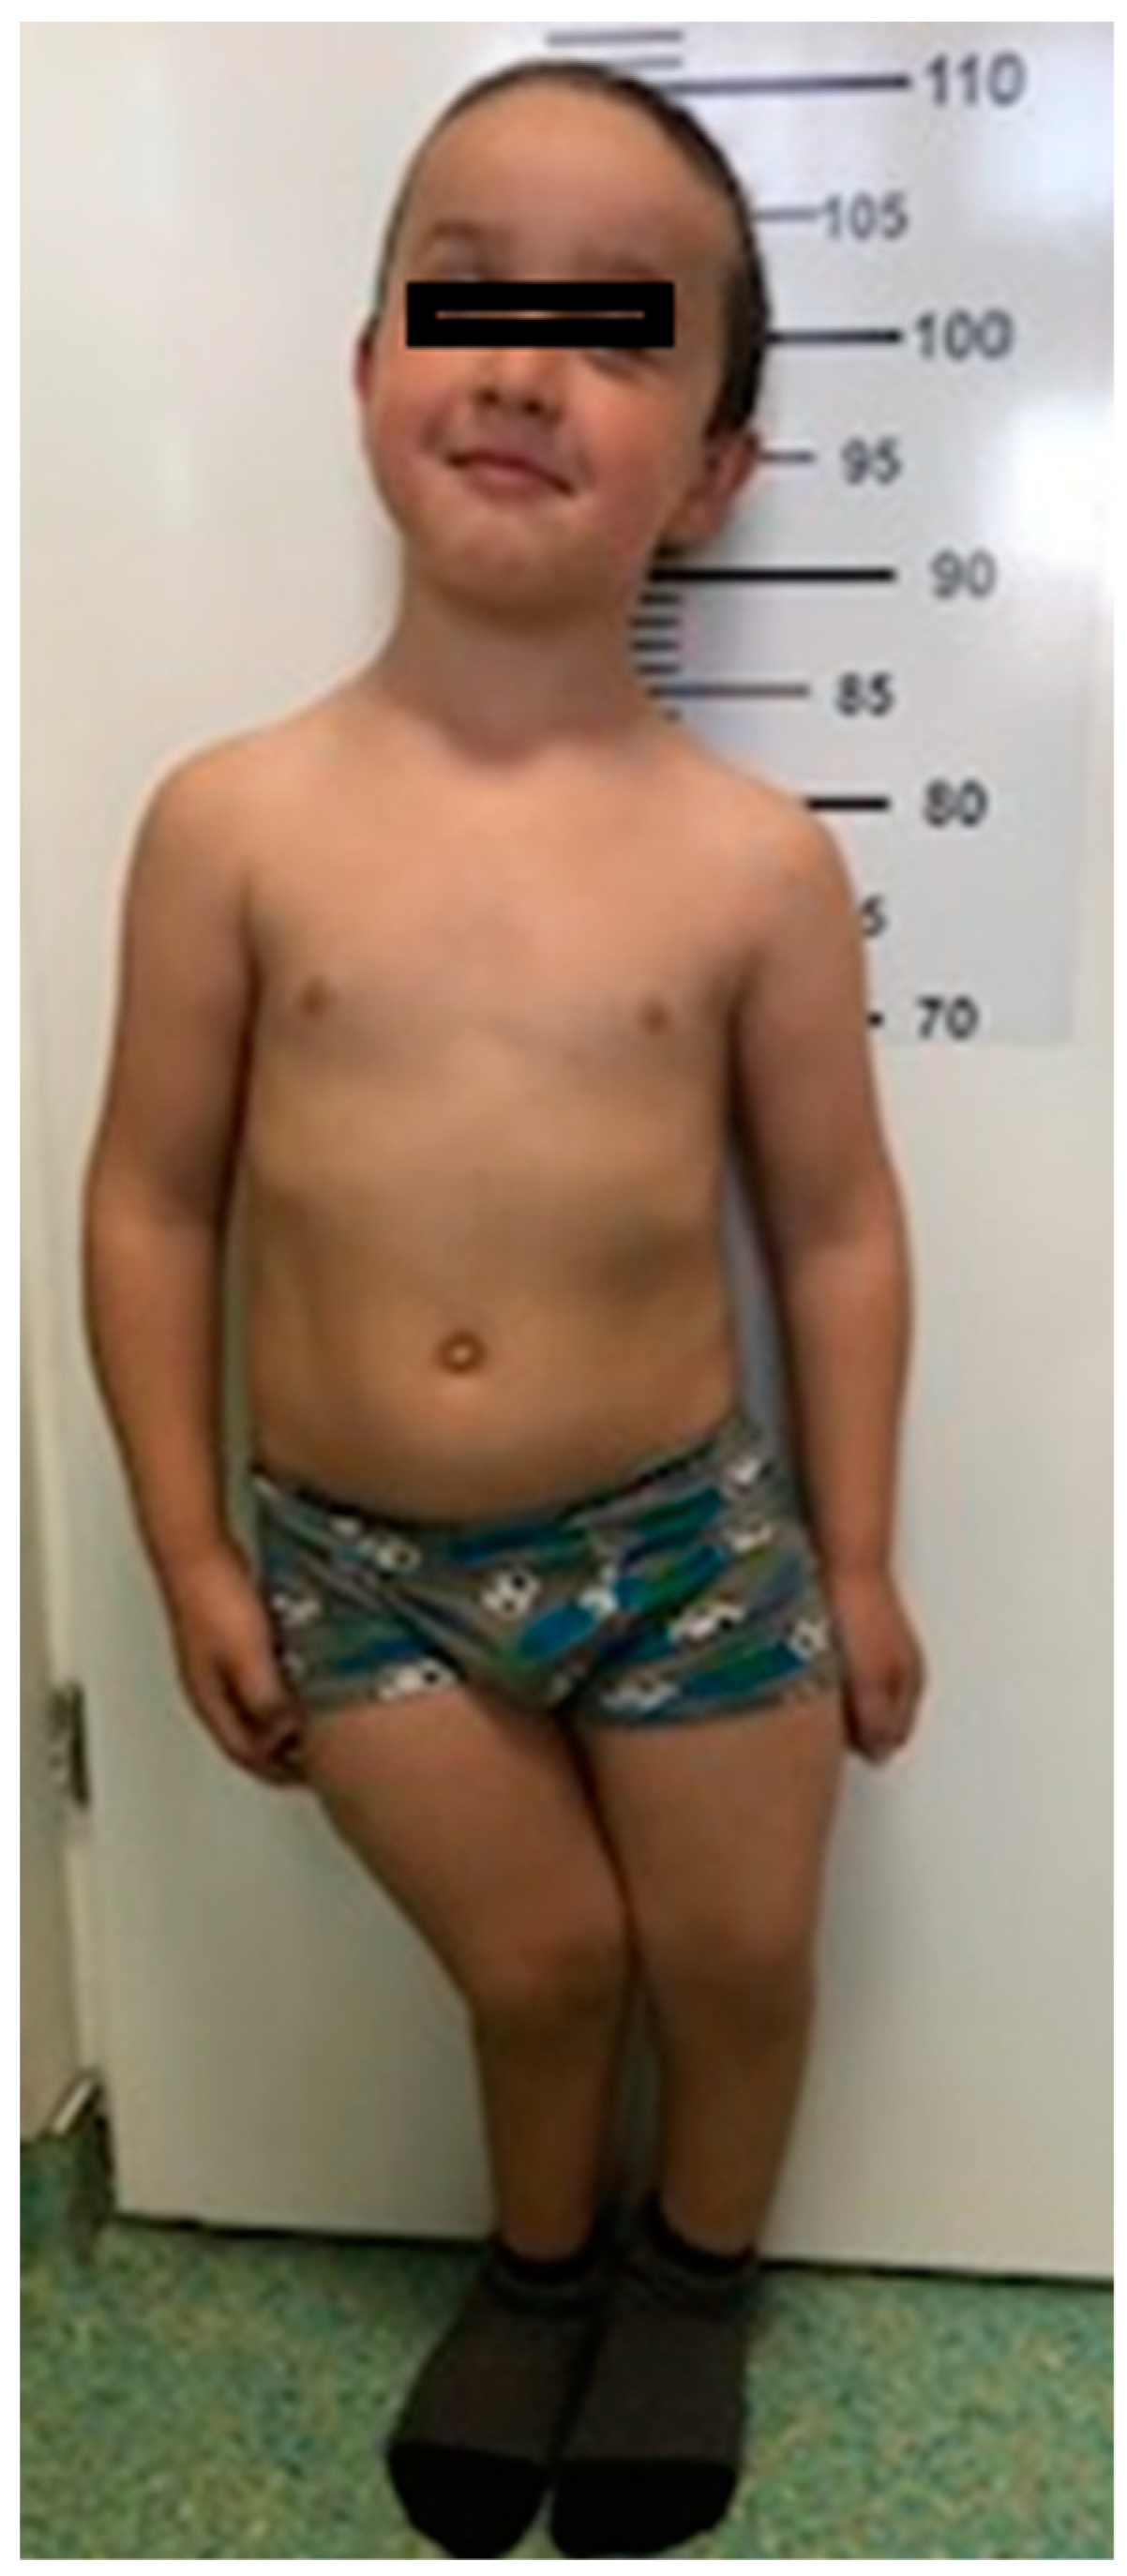

3.1. Morphological Evaluation of the Patients

| Craniofacial dysmorphism | macrocephaly: head circumference 53 cm frontal bossing flattened facies bilateral epicanthal folds, high arched palate | |

| Chest deformity | pectus excavatum, thoracolumbar scoliosis, Harrison’s groove and rachitic rosary | pectus excavatum, Harrison’s groove and rachitic rosary |

| Musculoskeletal abnormalities | thickened wrists and ankles, severe bilateral bowing of lower limbs (genu varum) | thickened wrists and ankles, genu valgum deformity (knees touching each other while the ankles remain spaced apart) |

| Walk | waddling gait | impaired |

| Walking fatigue | ++++++ | +++ |